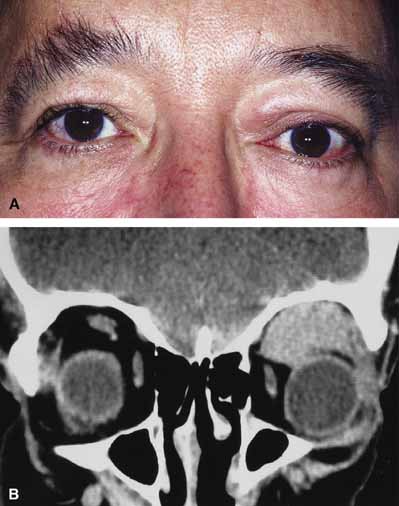

In some patients the orbitopathy is more aggressive and rapidly evolving with acute proptosis over 1 to 2 days, swelling of the lids and conjunctiva, diplopia, corneal exposure, and optic neuropathy (Fig. 6A). This presentation may be confused with disorders such as nonspecific orbital inflammation or carotid-cavernous fistula.44 The differential diagnosis of acute proptosis with enlarged extraocular muscles includes thyroid orbitopathy, vascular causes (arteriovenous fistulas), inflammation (orbital myositis, sarcoid), infection, primary invasive tumor, metastasis to the extraocular muscles.45,46

Fig. 6 A. A 56-year-old female presented with a 2-day history of proptosis, lid swelling, conjunctival chemosis/injection, and double vision. Thyrotropin (TSH) level was extremely low and a computed tomography (CT) scan revealed grossly enlarged extraocular muscles. A diagnosis of acute thyroid eye disease was made. B. Axial computed tomographt (CT) scan illustrating diffuse enlarged extraocular muscles characteristic of thyroid eye disease. C. Coronal computed tomography (CT) scan showing enlargement of extraocular muscles.

CT classically reveals enlarged extraocular muscles (Fig. 6B and 6C). One or all of the muscles may be involved and there is bilateral involvement in the majority. The most frequently involved muscle is the inferior rectus followed by the medial, superior, and lateral rectus (opposite to the spiral of Tillaux).40 The tendons of the affected recti muscles are typically not thickened, resulting in a characteristic fusiform enlargement of the muscle, whereas in myositis secondary to nonspecific orbital inflammation the tendons are generally thickened. Other signs are also useful to distinguish between the two. Bilaterally is unusual in myositis but common with thyroid. Thyroid usually has several muscles involved while myositis more often only has one muscle involved. In myositis the muscle border is more likely to be irregular or fuzzy with or without involvement of adjacent fat whereas in thyroid disease the muscle border is regular and there is no fat involved. Clinically there are also several distinguishing features. Myositis classically presents more rapidly and is associated with pain on extraocular movement. This is rare with thyroid eye disease. The eyelid signs (retraction, flare) are common with thyroid but absent in myositis.